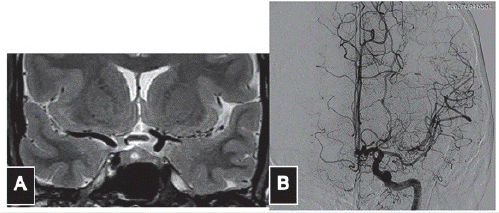

Mujer de 39 años de edad con antecedente de neurofibromatosis tipo 1, sin afectación familiar por síndromes neurocutáneos. Acudió a la consulta médica por un síndrome vertiginoso consistente en sensación de giro de los objetos, sin afectación auditiva ni de pares craneanos. Una resonancia magnética (IRM) de cráneo simple y contrastada (figura 1) mostró una hipoplasia del segmento A1 derecho, ausencia de la rama superior de M2 izquierda, sin la presencia de fenómenos isquémicos de dicho hemisferio; el vacío de señal en múltiples sitios en el territorio que debería estar ocupado por la rama superior de M2 sugirió un patrón de Moya-moya, que fue comprobado mediante arteriografía invasiva (figura 2). En esta se confirma el fenómeno de Moyamoya ("bocanada de humo") adyacente a la rama inferior de M2 izquierda; estos vasos neoformados reconstituyen el flujo en el tronco M2 superior ocluido crónicamente. Además hay una disminución del tamaño de los segmentos M1 y M2 de la arteria cerebral media izquierda. En ningún momento la paciente presentó déficit motor o sensitivo, u algún otro signo al examen físico que pudiera ser explicado por los hallazgos angiográficos.

Figura 1 Imagen de resonancia magnética donde se observa una configuración anómala de la porción M1 de la arteria cerebral media izquierda. (A). Angiografía cerebral donde observamos ausencia del tronco superior de M2 luego de la bifurcación (B).